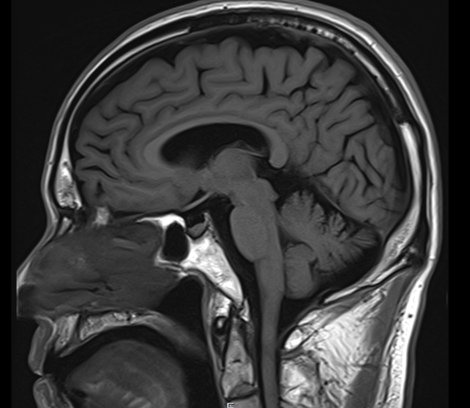

그런데 대학병원에서 이미 뇌 MRI까지 다 찍어보셨는데

특별한 이상이 없었다는 거예요.

뇌졸중이나 뇌출혈 같은 급성 문제도 아니고,

일반적인 뇌혈관 질환의 징후도 보이지 않고...

그림9.png 촬영 일시: 2025.05.11

<Fig 1. 정상 소견의 뇌 MRI>

그럼 대체 뭐가 문제일까요?